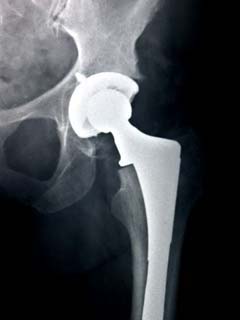

The total hip replacement implant is made up of the parts seen in the accompanying image. The acetabular shell is inserted as the “socket” part of the joint. Next, a liner (polyethylene in the shown case) is added as a cushion similar to cartilage present in a healthy joint. The stem part of the implant is inserted into the femur and the femoral head is attached to it making the “ball” portion of the joint. Once completely assembled, the implant is tested to be sure that it allows as much movement as healthy joints would.

The stem of the implant is typically made of a titanium alloy as well as a cobalt-chromium alloy. Some cobalt-chromium alloys also employ molybdenum. Cobalt-chromium alloys are also seen in the femoral head of the implant although in some cases other ceramics can be used. Finally, the acetabular shell can be made of various materials including metal, polyethylene with a very high molecular weight, or a combination of the two. The different parts of the implant all come in varying sizes and shapes and are custom made to allow for bone growth and proper fit in each patient. [2]